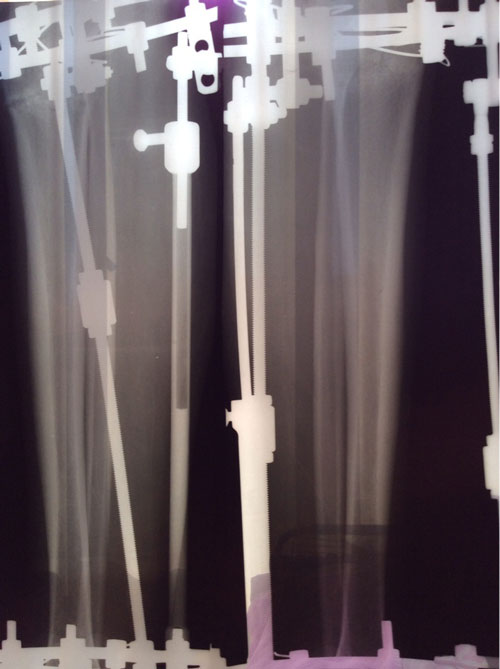

Ножки на фиксации, всё ок! Уезжаю домой на сращение!

Ножки на сегодня!